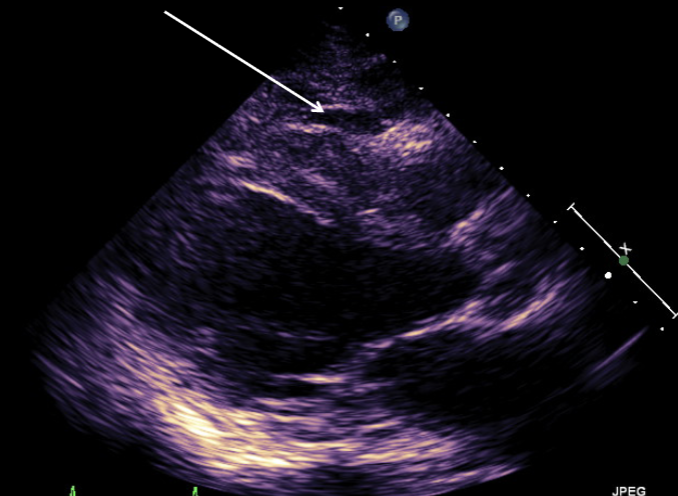

Classic LA Myxoma

echogenic mass located in the body of the LA in systole and prolapses through the mitral orifice in diastole

causes stenosis if large enough

narrowing of orifice

mimics MS